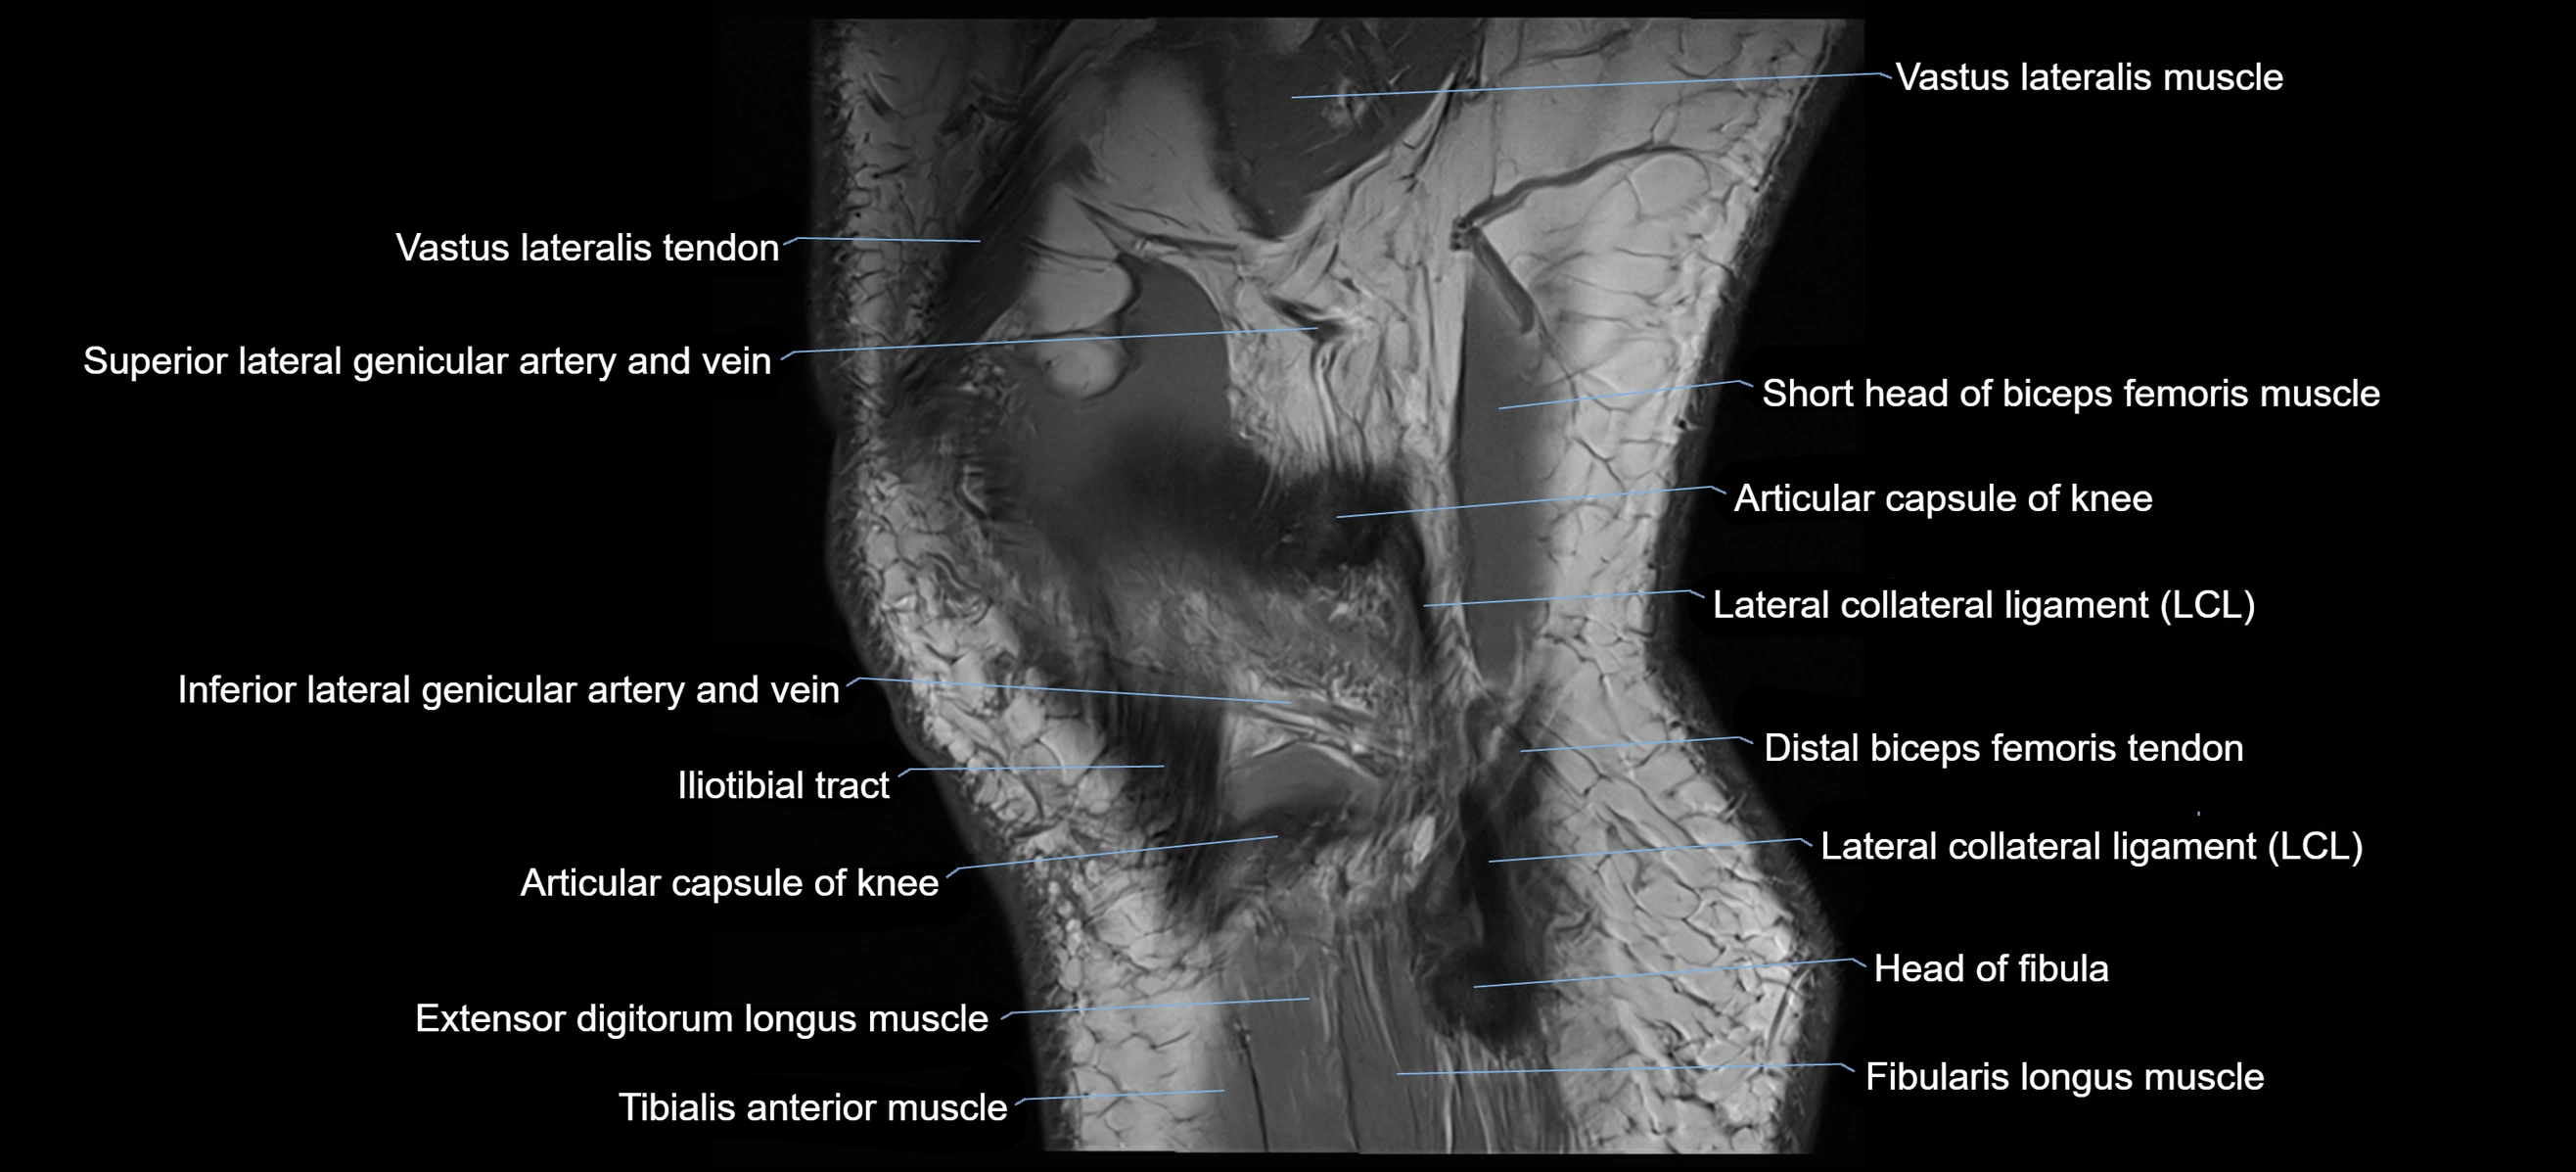

- Biceps femoris muscle (Short head)

- Distal biceps femoris tendon

- Distal vastus lateralis tendon

- Extensor digitorum longus muscle

- Fibularis longus muscle (peroneus longus muscle)

- Head of fibula

- Lateral collateral ligament

- Lateral condyle of femur

- Lateral epicondyle of femur

- Lateral gastrocnemius tendon

- Lateral head of gastrocnemius muscle

- Lateral sural cutaneous nerve

- Superior lateral genicular artery

- Superior lateral genicular vein

- Tibialis anterior muscle

- Vastus lateralis muscle